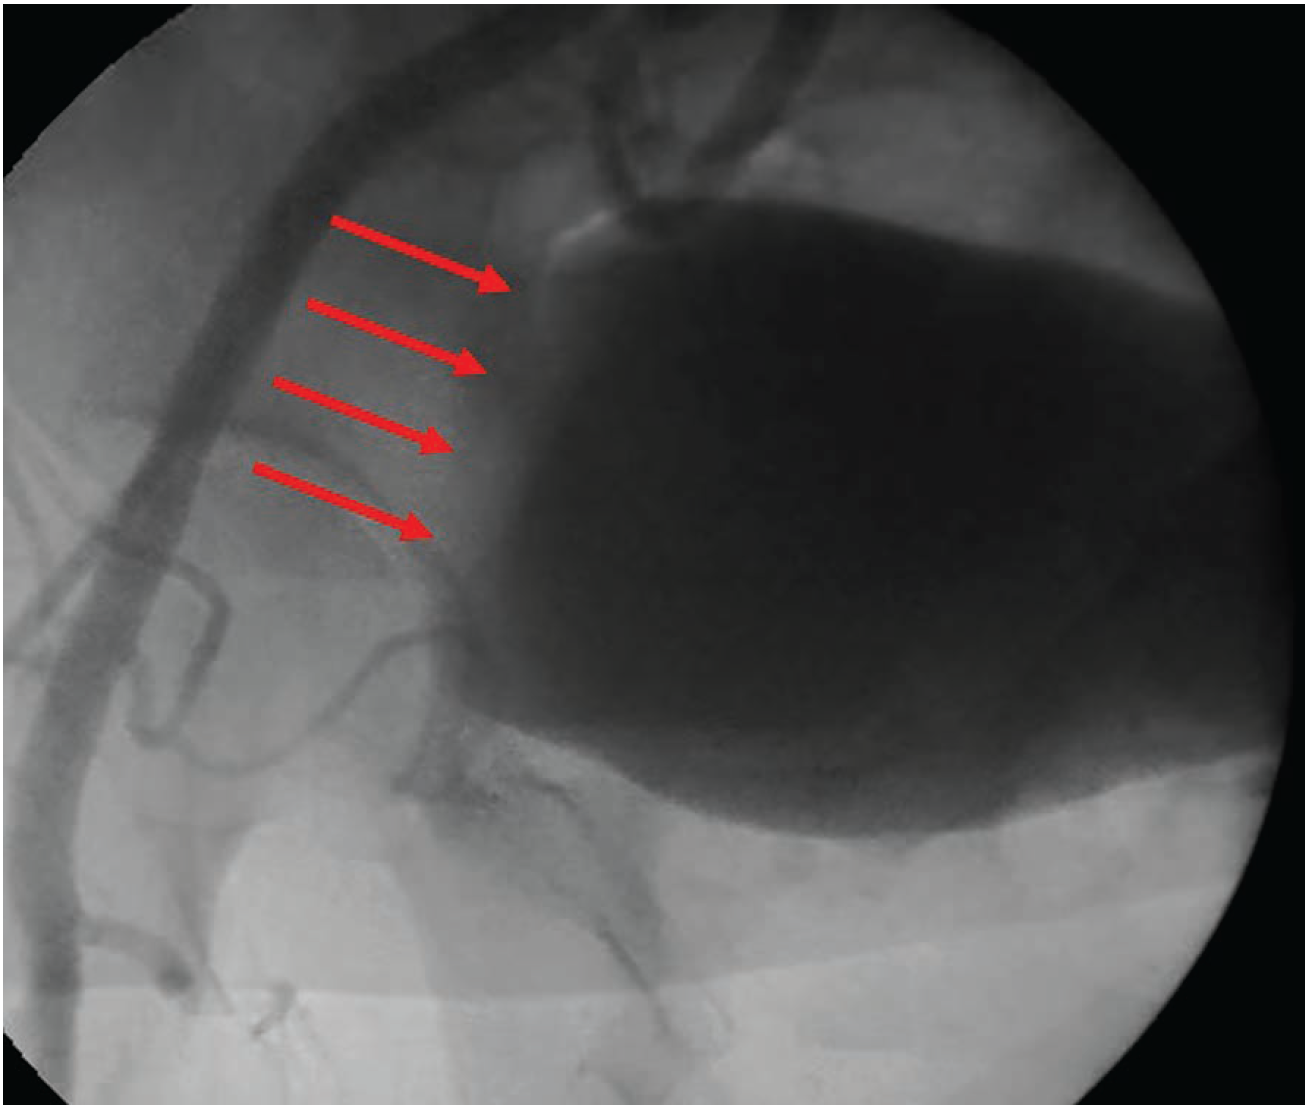

Figure 2 shows an injury to the IE that occurred due to 18-gauge needle laceration, which led to serious retroperitoneal bleeding (note yellow arrow of bladder displaced to the left from massive retroperitoneal bleed) that was only noted after the patient gradually became hypotensive during the case. Figure 3 shows an example of through-and-through sheath insertion of the IE that occurred during venous access that was properly managed with coils that extend distal and proximal to the hole. Of course, it goes without saying that proper access technique with a combination of fluoroscopy AND ultrasound could have prevented these incidents in the first place.

Courtesy of Dr. Curtiss Stinis.